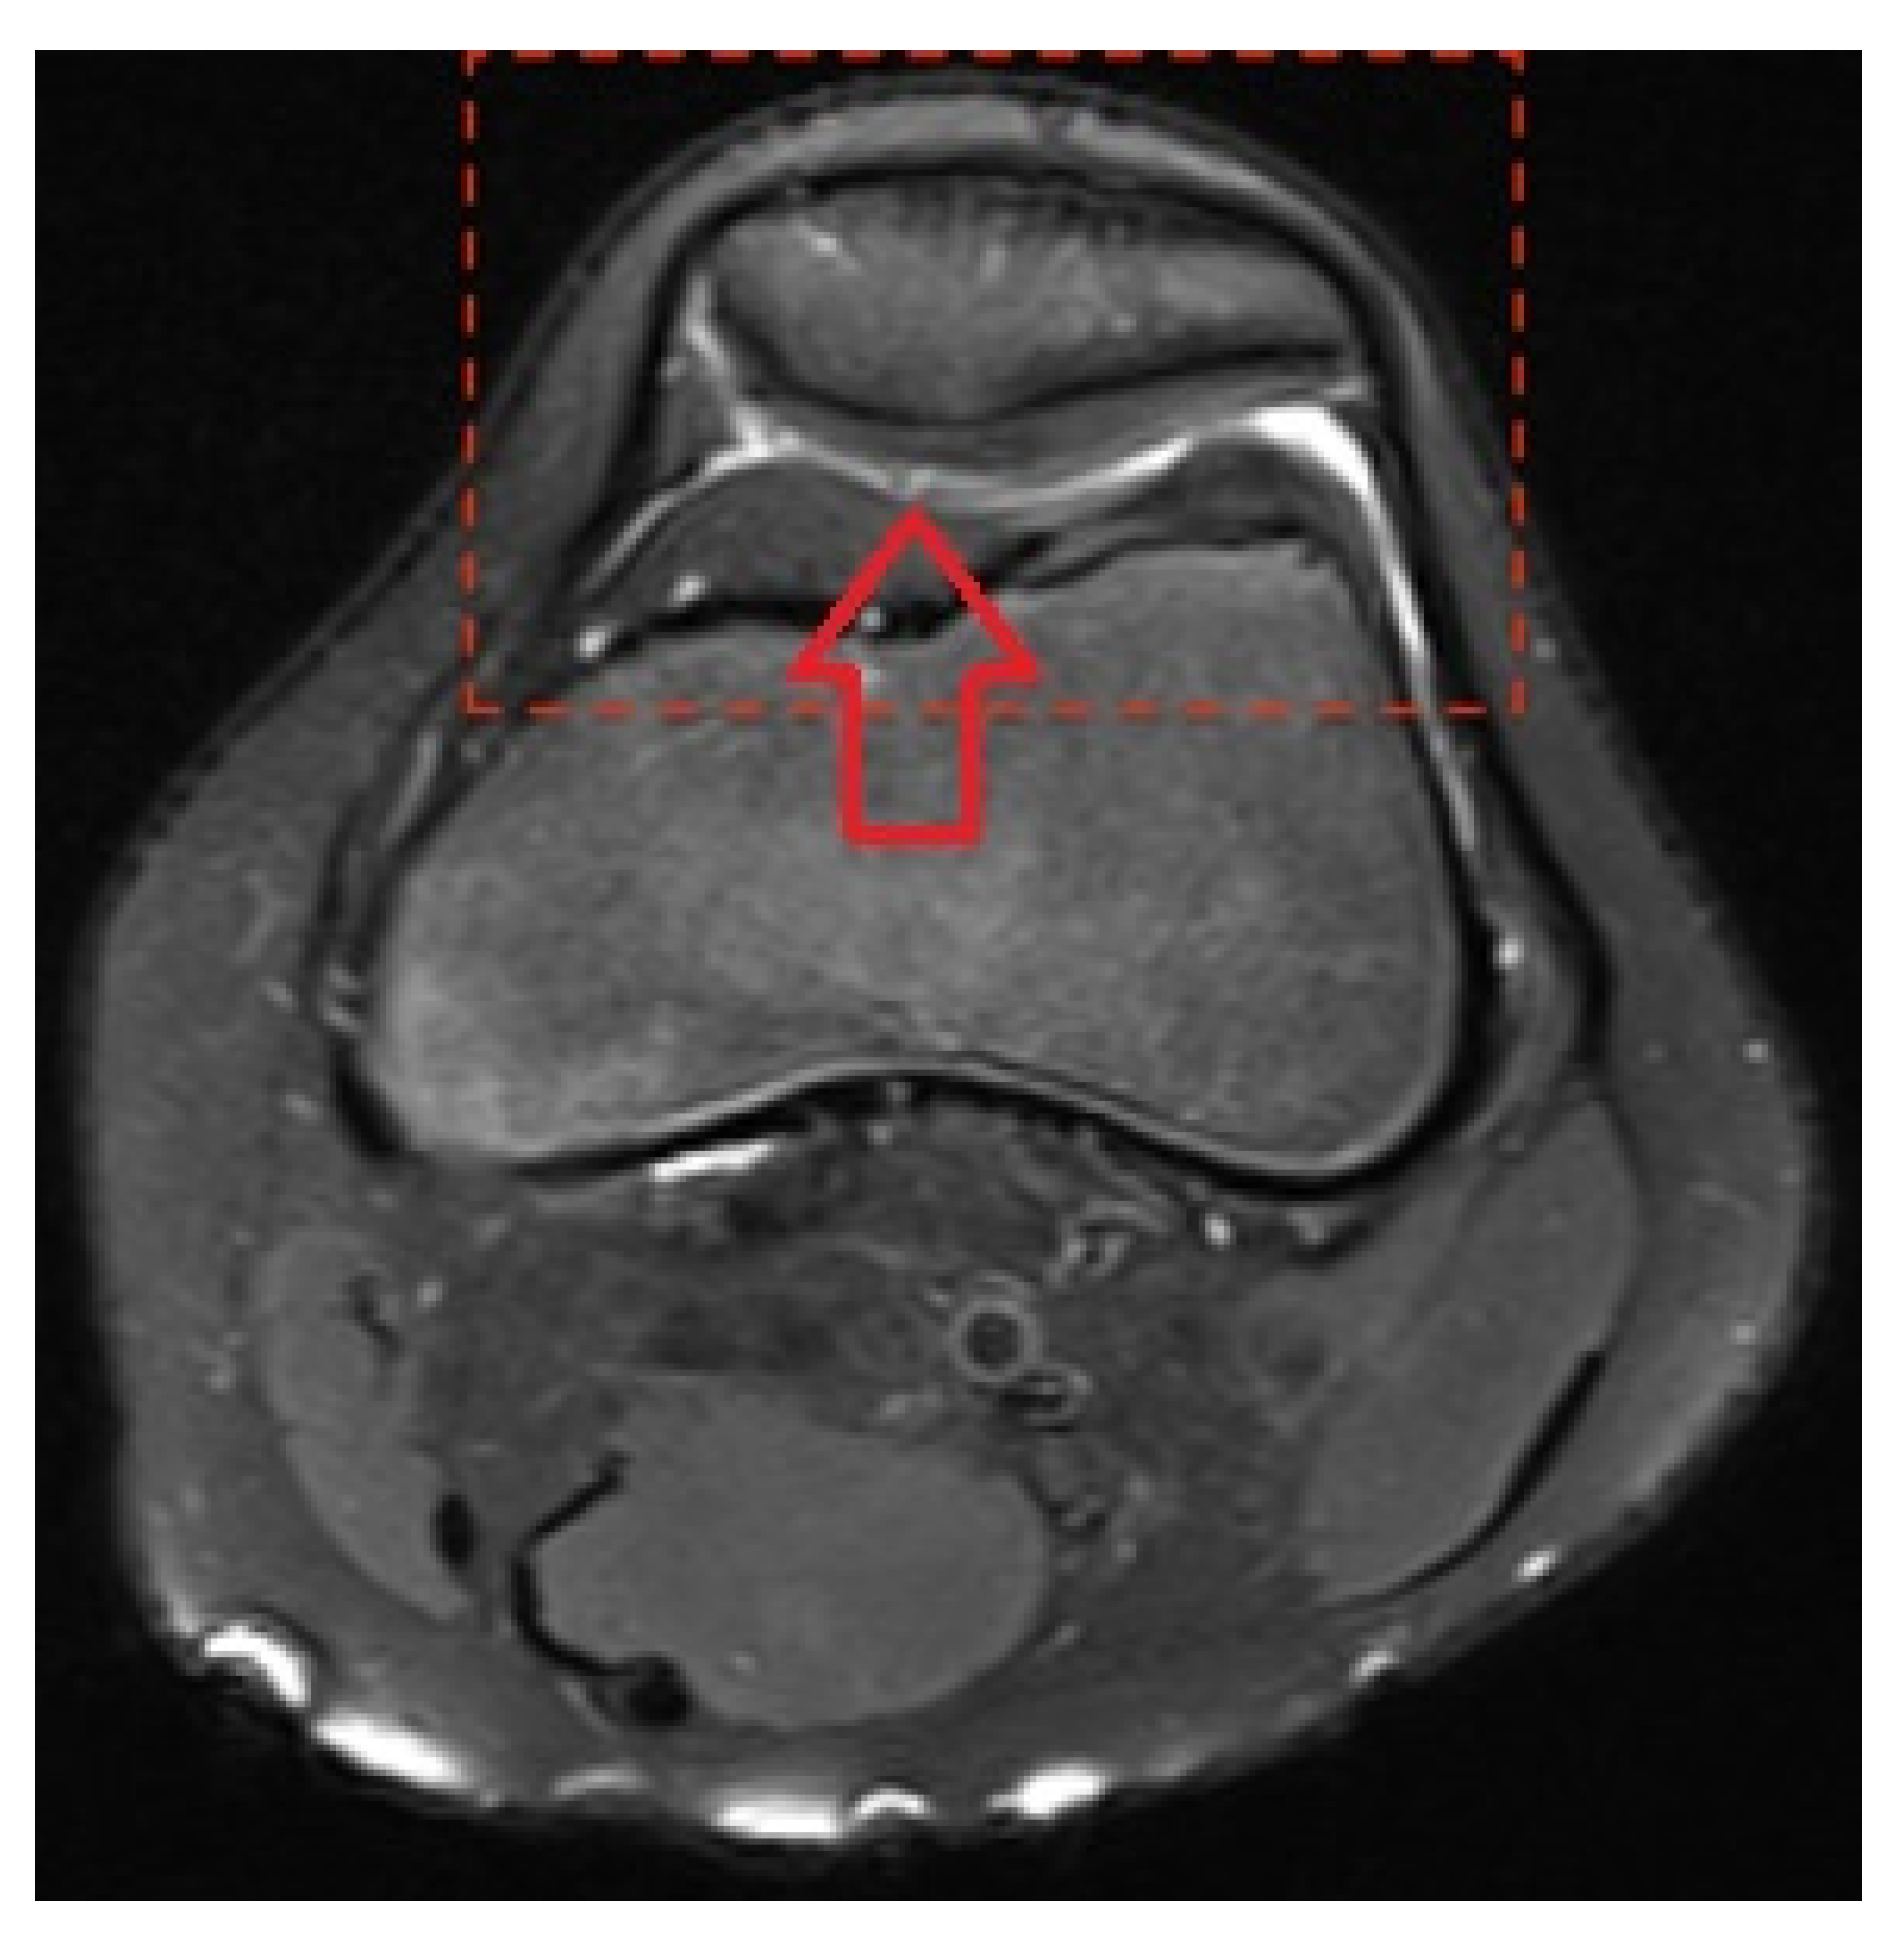

The Magnetic Resonance Imaging Pattern of the Lesions Caused by Knee Overuse in the Pediatric Population